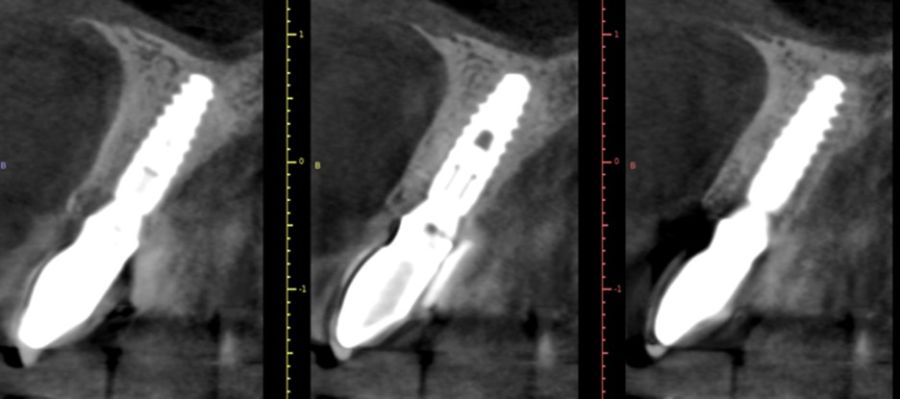

El implante se mantuvo en fase provisional durante un periodo aproximado de cuatro meses desde su colocación. Tras esta fase de provisionalización, se realizó la toma de impresión analógica mediante un coping de impresión personalizado, diseñado para reproducir de forma precisa el perfil de emergencia previamente modelado con la restauración provisional (Figuras 11 y 12). A partir de estos registros, se confeccionó e instaló la corona definitiva atornillada, con una oclusión suavizada para evitar sobrecargas del implante (2.1i). La imagen clínica (Figuras 13 y 14) y el CBCT postoperatorio (Figura 15) evidencian una situación clínica y radiológica favorable, con estabilidad de los tejidos periimplantarios a los cuatro años de seguimiento.

La preservación del volumen óseo periimplantario constituye otro aspecto crítico en los implantes inmediatos, especialmente a nivel vestibular. Estudios recientes han demostrado que la utilización de xenoinjertos óseos para el relleno del gap entre el implante y la pared alveolar contribuye a minimizar la reabsorción horizontal de la cresta ósea7. Asimismo, la combinación de injertos óseos con injertos de tejido conectivo ha demostrado mejorar significativamente el grosor y la estabilidad de los tejidos blandos periimplantarios, lo que resulta especialmente relevante en pacientes con biotipo fino y alta demanda estética8.

El éxito de los protocolos de implantes inmediatos con provisionalización inmediata depende de manera determinante de un diagnóstico exhaustivo y de una adecuada selección del caso. La evaluación minuciosa de los factores locales y sistémicos, el análisis tridimensional mediante CBCT, la planificación protésicamente guiada y la experiencia del clínico son elementos clave para poder llevar a cabo este tipo de tratamientos de forma segura y predecible.